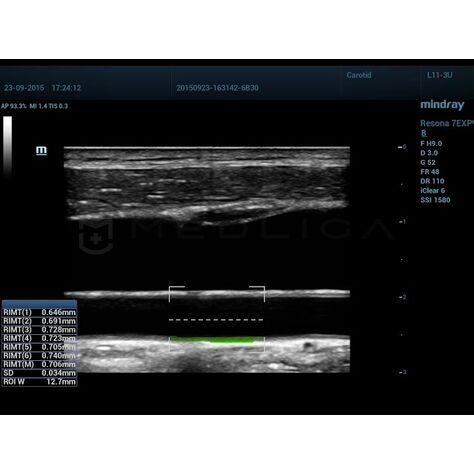

Определение размера КИМ - основной маркер для определения риска сердечно-сосудистых патологий. Практически все разработчики УЗИ сканеров вносят в функционал оборудования автоматические и ручные алгоритмы для измерения толщины стенки сонной артерии. Для осуществления измерений IMT применяется постобработка кинопетли, что в свою очередь имеет некоторые ограничения. Mindray разработали технология RIMT, с инновационными алгоритмами обработки полученных данных сканирования и гарантирует точное измерение комплекса интима-медиа.

Сравнение технологии RIMT и обычного режима IMT

- RIMT - новейшая технология и в разы превосходит традиционные измерения, например, точность RIMT выше в 16 раз, так как при RIMT происходит измерение ИМТ 6 сердечных циклах, а не 1 как при обычном IMT.

- RIMT (M) - средний показатель за 6 циклов

- SD - стандартное отклонение

- ROI W - ширина исследуемой области